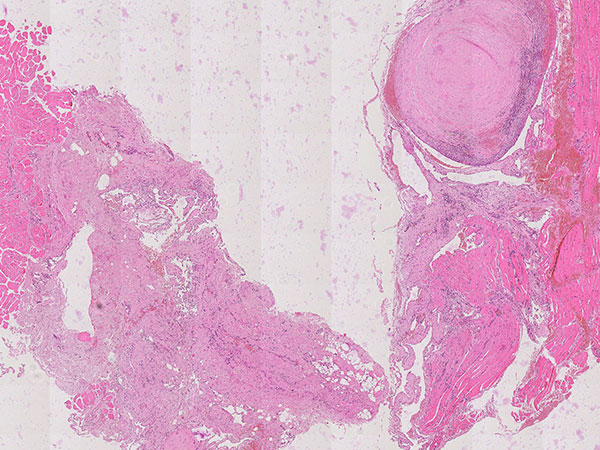

Hematoxylin & eosin stain, 21× magnification: A phlebolith already transformed into connective tissue is shown top right. Overall, as an indication of a vascular lesion, increased irregular vascular cavities are visible in the histopathological overview image.

Hematoxylin & eosin stain, 64x magnification: Layered, predominantly connective tissue appearance of the older, partially organized phlebolith. The phlebolith is surrounded by multiple proliferated, irregularly structured, thin-walled vascular spaces.